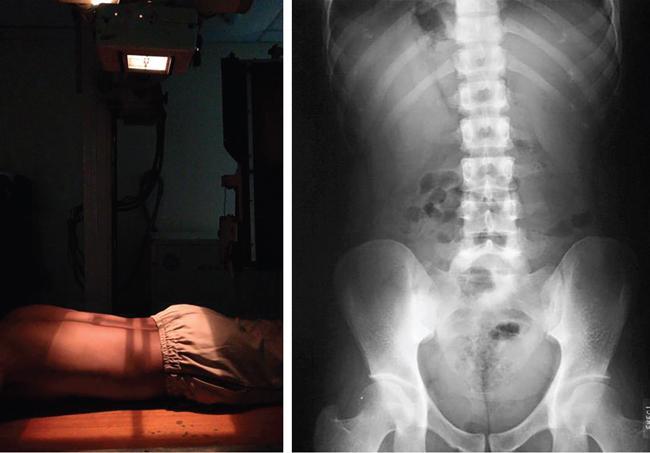

UNDERSTANDING THE ADULT ABDOMINAL RADIOGRAPH: TECHNIQUES AND INTERPRETATION Tanvi Modi Radiography of the abdomen is a common practice for the evaluation of abdominal organs. The anatomy and pathology of digestive, hepatobiliary and genitourinary systems can be assessed using radiographs, either as a stand-alone practice or as a primary imaging modality followed by contrast studies, ultrasound or cross-sectional imaging. In addition, abnormalities of the musculoskeletal or integumentary system can also be deduced on the basis of abdominal radiographs. This chapter intends to give an overview on the techniques and positioning in abdominal radiography as well as interpretation of normal and abnormal features. While superior imaging modalities such as ultrasound, computed tomography (CT), magnetic resonance imaging, capsule endoscopy and the likes have taken over abdominal imaging by and large, radiography still holds a pivotal role in certain situations and conditions, such as: The standard abdominal radiograph is taken in supine position and anteroposterior projection. This is also popularly known as the KUB (kidneys-ureters-bladder) radiograph. Previously, supine as well as erect radiographs were performed in all patients; however, this is not commonly done due to high-radiation dose. For all indications of abdominal radiography, including acute abdomen, supine radiographs are sufficient in terms of radiographic diagnosis, with the exception of perforation for which an erect chest or lateral decubitus radiograph can be performed if there is clinical suspicion. Patient should lie supine on the imaging table with median sagittal plane at right angles to the table and coincident with the midline of the table (Fig. 7.1.1.1). The body is divided into equal right and left halves by the median sagittal which passes through the sagittal suture of the skull. Pelvis should be adjusted so that the anterior superior iliac spines are equidistant from the table top. Gonadal shields, in the case of male patients, should be placed with the upper edge of the shield at the level of pubic symphysis. Although rarely used for female patients, these should be positioned between the anterior superior iliac spines and the pubic symphysis. The centre point of the image receptor should be approximately located at a point 1 cm below the line joining the iliac crests. The X-ray beam should be in a vertical direction, perpendicular to the table top and image receptor at the centre point. Collimation should be such that the soft tissue and subcutaneous region along lateral aspects of the abdominal cavity should be covered within the image. Also, the superior extent involving diaphragm and inferior extent involving the inferior pubic rami is important to look for any lower chest pathologies or any inguinal hernia. 35 × 43 cm (14 × 17 inches) in portrait orientation. On an average, abdominal radiograph exposes a patient to a dose of approximately 1.5 mSv, which is equivalent to 75 chest radiographs or 1/6th dose of a standard CT of the abdomen. The entrance skin dose is approximated to be 4 mGy. At such an effective dose, the additional lifetime risk of fatal cancer is 1 in 30,000. The exposure time is kept short. Patient is asked to exhale completely and hold their breath, with exposure taken at this point of full expiration to ensure imaging of abdominal organs in their natural positions. Modifications of this technique can be made depending on patient habitus and clinical condition. Kilovoltage peak (kVp) should be set to allow adequate visualization of abdominal soft tissue structures as well as semiopaque renal and biliary calculi. Average kVp is set at 70–85 kV. 102 cm (40 inches) Grids are commonly used to reduce scatter radiation. Placement of side marker on the image receptor at the time of radiographic exposure is essential. Bowel pattern depiction should be such that there is minimal lack of sharpness. Standard guidelines for abdominal radiography dictate that the radiograph should extend from the diaphragm up to the level of inferior pubic rami and must include the lateral abdominal wall musculature. The abdomen is divided into four quadrants on the basis of two perpendicular lines (Fig. 7.1.1.7). The vertical line passes through the mid sagittal plane and crosses the umbilicus and symphysis pubis. The horizontal line is a transverse line across the umbilicus at 90 degrees to the vertical line and is situated at the level of L4–L5 intervertebral disc. The quadrants are as follows: Another division system is dividing the abdominopelvic cavity into nine regions using two vertical and two horizontal planes (Fig. 7.1.1.8). The vertical planes, also known as the right and left lateral planes, are parallel to the midsagittal plane between midline and anterosuperior iliac spines on either side. Of the two horizontal planes, the upper transpyloric plane is at the level of lower border of L1 and the lower transtubercular plane is at the level of L5. The nine regions are: On a standard radiograph, the exposure should be such that the stomach, bowel loops, outlines of liver, spleen, kidneys, psoas muscles should be well identified. Also, lumbar transverse processes should be seen. Arch of the pubic symphysis should be visible to evaluate bladder region. A well-centred film without rotation will demonstrate bilaterally symmetrical lower ribs, iliac wings, ischial spines and obturator foramina. Different structures seen on an abdominal radiograph can be classified into five basic densities: Identification of different structures depends on the relative degree of contrast between their densities. The demarcation is clearer in chest and is diminished in abdomen due to relative similar soft tissue density of various structures. On a normal radiograph, relatively large amounts of gas in stomach and colon with minimal small bowel gas can be seen. Further, colonic gas can vary from negligible to extensive, mimicking obstruction pattern; however, usually the gas is enough to delineate colonic haustral pattern. Faecal matter gives a mottled appearance to colonic gas. Short-air fluid levels on an erect radiograph may be seen even in normal cases. The normal appearance of small bowel loops on an abdominal radiograph follows the rule of threes: Stomach is seen in the left upper quadrant and is visualized when distended with air. It is commonly seen extending from T11 to L2 level. Common feature identifying the stomach is the fundal gas which is usually seen as an air fluid level within the gastric lumen. Small bowel loops are distributed to the centre of the abdominal cavity and large bowel loops are peripheral. Duodenum is predominantly situated in right upper quadrant. It extends to left upper quadrant in the region of duodenojejunal flexure. Jejunum occupies the left upper and lower quadrants and is easily identified due to the presence of thick, numerous, closely spaced valvulae conniventes (Fig. 7.1.1.9A). The ileum occupies both lower quadrants and extends into right upper quadrant. Ileum has few and less prominent valvulae as compared to jejunum (Fig. 7.1.1.9B). Ascending and descending colon are retroperitoneal and have relatively fixed positions along lateral aspect of the abdominal cavity on either side. Transverse and sigmoid colon, on the other hand, may have a variable position due to their mobility along mesocolon and redundant pattern. These can be identified with confidence on account of haustrations and faecal matter (Fig. 7.1.1.10). Haustrations are usually well seen in ascending and transverse colon and poorly delineated beyond splenic flexure. Caecum is in the right lower quadrant, though it may be mobile or pulled up. Rectal gas is usually seen in the midline at the level of pelvis and its presence rules out large bowel obstruction. All these positions may vary due to anatomical conditions such as malrotation or pathological conditions, for example volvulus. Liver, spleen and renal outlines cannot be completely traced with precision due to the overlap by bowel loops. On a frontal projection, the liver appears as a triangular structure occupying right and left hypochondrium and epigastric region. Occasionally, the right lobe may be seen extending lower than the right renal shadow. This is a normal variant known as Reidel’s lobe. Gall bladder is situated in the posterior and inferior region of the liver and any pathology of the gall bladder should be looked for in this region. On a lateral radiograph, the gall bladder is anterior to the midcoronal plane. This helps in distinguishing gall bladder calculi from renal calculi, which will be more posteriorly situated. Spleen is seen in left upper quadrant/left hypochondrium, flushed to left lower ribs and left hemidiaphragm. Pancreas is present in the epigastric region (right and left upper quadrants) and is usually not identified in the absence of a pathology. The kidneys are bean-shaped retroperitoneal organs which are seen on either side of the vertebral column and lateral to psoas muscles. Due to the presence of liver on the right side, this kidney is slightly lower in position as compared to its contralateral counterpart. The visualization of kidneys on radiographs is facilitated by the surrounding fatty capsule. Kidneys lie between T11–12 and L2 level, with left kidney 1 cm higher than the right. Psoas muscle shadow can be normally seen along lateral aspect of lumbar spine bilaterally and is mildly concave (Fig. 7.1.1.11). Abdominal wall muscles are not routinely assessed on radiography; however, inclusion of lateral abdominal wall (muscles as well as subcutaneous plane) is a must while performing radiography. The flank stripe or the properitoneal fat stripe is a fat density linear concavity seen along lateral abdominal wall (Fig. 7.1.1.11). It is bound by the paracolic gutters and air-filled ascending and descending colon. All the solid organs in the abdomen are identified due to the fat density outlining them. Distortion of these fat lines helps in identifying organomegaly or focal mass lesions. The dome of urinary bladder is outlined by fat, which aids in differentiating its density from other soft tissue structures of the pelvis. Not all calcifications seen on abdominal radiograph are abnormal. Some may depict age-related changes such as vascular calcifications involving abdominal aorta, pelvic vessels, splenic artery in the region of left upper quadrant. Within the pelvis, phleboliths may be seen and mistaken for urinary calculi. Assessment of lumbosacral spine, iliac bones and femoral heads can be made on the basis of plain radiography. Degenerative changes may be commonly seen. Lower ribs can also be evaluated for pathologies. Dilated small bowel loops with rounded soft tissue density in midline over umbilical region suggests obstruction secondary to umbilical hernia. Pneumoperitoneum must be looked for in all cases of acute abdomen. While erect chest and left lateral decubitus radiographs can detect even 1 mL of free air, there are multiple signs on supine radiograph to suggest this diagnosis, for example Rigler’s sign, falciform ligament sign, football sign (Figs. 7.1.1.24 and 7.1.1.25). Retroperitoneal perforation may demonstrate air outlining psoas muscles and retroperitoneal organs. Small amount of free air may persist in the abdominal cavity up to 3 weeks after surgery, although it usually resolves within a week. Clinical history is important in such cases. Air foci within the bowel wall may represent bowel ischaemia/strangulation. Linear gas patterns in right hypochondrium may be due to two causes, that is pneumobilia and pneumoporta. The former can be seen normally postbiliary surgery, sphincterotomy, ERCP or in the case of abnormal fistulous communication between bowel and biliary tree (Fig. 7.1.1.26A). Pneumoporta (Fig. 7.1.1.26B) is a red flag and warrants further investigation to look for conditions such as mesenteric ischaemia and toxic megacolon. Pneumobilia is more centrally located whereas air shadows in pneumoporta are seen reaching up to periphery of liver. Air foci over renal shadows (Fig. 7.1.1.27), gall bladder or pancreas, in the absence of recent procedural history, suggest fulminant infection and mandate urgent intervention. Central midline calcific foci between T9 and T12 vertebrae can be attributed to calcific pancreatitis (Fig. 7.1.1.28). In the left upper quadrant, areas of calcification seen involving a shrunken spleen may be seen in autosplenectomy. In right upper quadrant, calcified gall stones may be seen. These tend to be small, multiple, uniformly circumscribed and ring-like in appearance with central translucency (Fig. 7.1.1.29A). Mercedes Benz sign, a triradiate pattern of gas lucency, is associated with gallstones. In contrast, renal calculi are more commonly solitary, irregular, of homogenous density, conform to renal calyceal or pelvic outline (Fig. 7.1.1.29B) and are sometimes of staghorn configuration. On lateral view, the gall stones are more anteriorly located as compared to renal calculi, which may be partly superimposed on lumbar vertebrae. Ureteric calculi tend to overlap bony structures such as lumbar transverse processes (Fig. 7.1.1.29B) or sacroiliac joints. Extensive or patchy, curvilinear calcification of gall bladder wall is known as porcelain gall bladder which is often associated with malignant transformation. Calcification involving adrenal glands may be secondary to infection or haematoma, or a congenital condition known as Wolman’s disease where there is bilateral involvement. Discontinuous discrete midline tram track calcification in the abdomen may indicate atherosclerotic changes in abdominal aorta and branch vessels. However, when the calcification is in a globular pattern and seen below the level of L2 vertebra, aortic aneurysm should be suspected (Fig. 7.1.1.30). Appendicoliths, though not commonly seen, may sometimes be detected in right iliac region. Pelvic calcifications: vesical calculi, distal ureteric or vesicoureteric junction calculi, calcified fibroids, ovarian dermoid with tooth-like calcifications (Fig. 7.1.1.31) may be the cause of abdominal pain and should be diligently looked for. Vesical calculi are usually more large and central in location whereas calcification due to fibroids may be more lateral. Schistosomiasis is another cause of bladder wall calcification, as is calcification of bladder tumours. Phleboliths tend to be bilaterally symmetrical, with a lucent centre unlike ureteric calculi. While it is believed that phleboliths are located below the level of ischial spines and ureteric calculi above, this is not always true and should be confirmed with CT. Fluid may collect adjacent to properitoneal fat line, forming a linear soft tissue density separating the fat line from the ascending or descending colon. Hellmer’s sign demonstrates medial displacement of lateral edge of liver (hepatic angle), due to fluid collection or ascites. Gross ascites may appear as generalized abdominal haziness or diffuse increased density of pelvis. Abscesses can involve any solid organ and in such cases may be difficult to demonstrate on plain radiography alone. Enlargement of organ or faint gas densities within can be suggestive of the same. In the case of peritoneal abscess, mottled density due to air, fluid and necrotic contents point towards this diagnosis, especially in right iliac fossa in association with appendicitis. Retroperitoneal abscess, similar to any retroperitoneal mass, may cause displacement of retroperitoneal structures (Fig. 7.1.1.32). Subdiaphragmatic abscesses may show concomitant ipsilateral pleural effusion (Fig. 7.1.1.33). These should be differentiated from Chilaiditi syndrome. Fluid and soft tissue lesions present with the same density on radiographs. While it is difficult to characterize the lesion and organ of origin, clues for the same can be provided by organomegaly (Fig. 7.1.1.34), distortion of fat surrounding solid organs, displacement of bowel loops or solid organs. For example, a retroperitoneal lesion may cause anterior or inferior displacement of kidney, a pelvic mass may cause upward displacement of small bowel loops. Different densities such as fat or calcification may help in identifying organ of origin (e.g. fat and tooth densities seen in ovarian dermoid). Convexity of margins of psoas muscle on an abdominal radiograph can be due to haematoma, abscess or intramuscular tumour. Radiographs are performed for the initial diagnosis of foreign body in the abdomen including type, number of foreign bodies, location, size and shape (Fig. 7.1.1.35). Radiolucent foreign bodies such as wood, plastic, chicken bones will not be easily identified on radiography. Low kVp (65–70 kVp) can increase contrast and help identify these objects. In addition to an abdominal radiograph, chest radiography is also performed to exclude aspiration or oesophageal location of foreign body. Ingested or introduced foreign bodies may cause complications such as obstruction, perforation, fistula formation and sepsis. Hence, once their presence is confirmed, follow up radiography must be performed until they are eliminated. One must look for fractures/dislocation injuries involving the vertebrae or pelvic bones, especially after history of trauma. Lucent expansile lesions or sclerotic bony deposits which represent neoplasms, absent pedicle sign in cases of metastasis, metabolic bony changes such as rugger jersey appearance, Paget’s disease, arthropathies such as ankylosing spondylitis with bamboo spine appearance and sacroiliitis (Fig. 7.1.1.36) are some of the conditions which may be diagnosed based on an abdominal radiograph. Overlap of bowel loops over iliac blades may lead to a misdiagnosis of lucent lesions and should be evaluated with caution. Basal pneumonia may be the cause of acute abdominal pain and should be looked for in abdominal radiography. Similarly, pleural effusion, pericardial effusion, calcified pleural plaques, achalasia, interstitial fibrosis are few other findings that can be seen in lower chest on an abdominal radiograph. Basilar atelectasis can give a deceptive appearance of pneumoperitoneum (Fig. 7.1.1.37). Surgical clips, commonly in right hypochondrium after cholecystectomy, drainage tubes, ventriculoperitoneal shunts, femoral line catheters, IVC filters, stents (vascular, renal, biliary) (Fig. 7.1.1.38), stoma bags, contraceptive devices are some structures that may be seen in an abdominal radiograph. Correct knowledge of patient history and normal locations of these structures prevents misdiagnosis. Certain artefacts may be projected upon the radiograph due to surface structures such as trouser buttons, body piercing, sequins over clothing and should not be considered as a pathology. Multiple skin surface nodules in cases of neurofibromatosis, soft tissue focal swellings, such as abscesses, lipomas, haematomas, desmoid tumours and malignant lesions may be incidentally seen on radiography. These can be further evaluated using ultrasound or CT. Subcutaneous emphysema is another finding that may be seen in lower abdominal wall secondary to retroperitoneal perforation or diffusely along abdominal wall in the case of bowel perforation (Fig. 7.1.1.39). Foreign bodies such as bullets and pins may be seen lodged in abdominal wall. A systematic approach to abdominal radiographs is important for accurate diagnosis as follows: Despite the development of newer techniques for imaging of the abdomen, plain radiography still holds an important place in the initial assessment of acute abdomen. Positive and negative findings on an abdominal radiograph can direct further investigation. Ideal positioning, recognition of normal appearances and keen scrutiny for pathologies is a sine qua non for radiologists reading a plain film of the abdomen. OESOPHAGOGRAM Padma V. Badhe, Vikram Reddy, Sultan Moinuddin Shaukatali, Zillani Alam, Ravi Varma, Abhishek Bairy, Dasari Ravikiran, Revati Tekwani, Soniya Patankar, Megha Nair, Gautham Shankar Oesophagogram is the process of obtaining radiological images and simultaneous motion recording to evaluate function and disorders of pharynx, oesophagus and proximal stomach. Oesophagogram is usually done primarily to evaluate dysphagia. Some of the common indications are oesophageal motility disorders, strictures, gastro-oesophageal reflux disease (GERD) and suspected masses. It can also be used to detect uncommon anomalies like vascular rings/slings and aberrant anatomy. It also helps to evaluate further in cases where there is inability to pass upper GI scope. Double-contrast oesophagogram is mainly indicated in early mucosal disease like erosion, polyp, infection and tumours. If a motility disorder is suspected, dynamic technique (e.g. videofluoroscopy) is used for dysphagia or aspirations in cases of stroke, neuromuscular disorders, post head and neck surgery or radiation. Barium oesophagogram is contraindicated in suspected cases of perforation and tracheoesophageal fistula, aspiration, rarely if there is hypersensitivity to barium suspensions. It is also contraindicated in suspected oesophageal perforation where a water-soluble contrast agent is more suitable. However, ionic water-soluble contrast agent is better avoided in cases of aspiration or fistula with airway. The contrast examination of the pharynx is dangerous in cases of acute epiglottitis and must be ruled out on plain radiograph. An 80% w/v barium suspension is used in full column views. However, 200%–250% w/v barium suspensions is usually required for mucosal relief films. The barium sulphate mixture is fed to the patient either by spoon, by glass, or through a drinking straw, depending on its consistency. In videofluoroscopy, the pharyngeal phase of swallowing is usually safer with barium pudding than with thick barium and safer with thick barium than with thin barium. However, if the major abnormality is poor pharyngeal contraction leading to stasis in the piriform sinus (and epiglottic tilt is normal), a thin liquid is safer. Epiglottic motility is better assessed with thin barium because thick barium often obscures the epiglottic tip. Fluoroscopic equipment capable of cine fluoroscopy and capability for rapid sequence spot images (high frame rate) is needed for this examination, Barium suspension, straw, glass, Lead apron and radiation protective equipment. The patients are instructed to fast after midnight before the day of the examination. The pharynx should be made as dry as possible during the examination as high-density barium adheres to dry pharyngeal mucosa. Activities like smoking, chewing gum and lozenges must be abstained before the procedure as they impair barium coating by increasing the salivary secretion. Regular oral medications must be taken with sips of water; however, insulin must be skipped on the morning of examination. The major principles of a good oesophagogram includes mucosal coating, distension and projection. A routine oesophagogram consists of screening of the oral, pharyngeal and oesophageal phases of swallowing, single and double-contrast examination of pharynx, single contrast, double-contrast and mucosal relief views of the oesophagus. In cases of dysphagia, the examination is tailored depending on whether the symptoms are either pharyngeal or oesophageal and initial fluoroscopic findings. If patients’ symptoms are suggestive of oral or pharyngeal disorder then pharynx is evaluated first. Similarly, if patient is suspected to have thoracic oesophageal disease then, double-contrast examination of the oesophagus is performed before the pharyngeal evaluation. During an oesophagogram the positioning of the patient varies according to the type of examination (Table 7.1.2.1).

Patient positioning